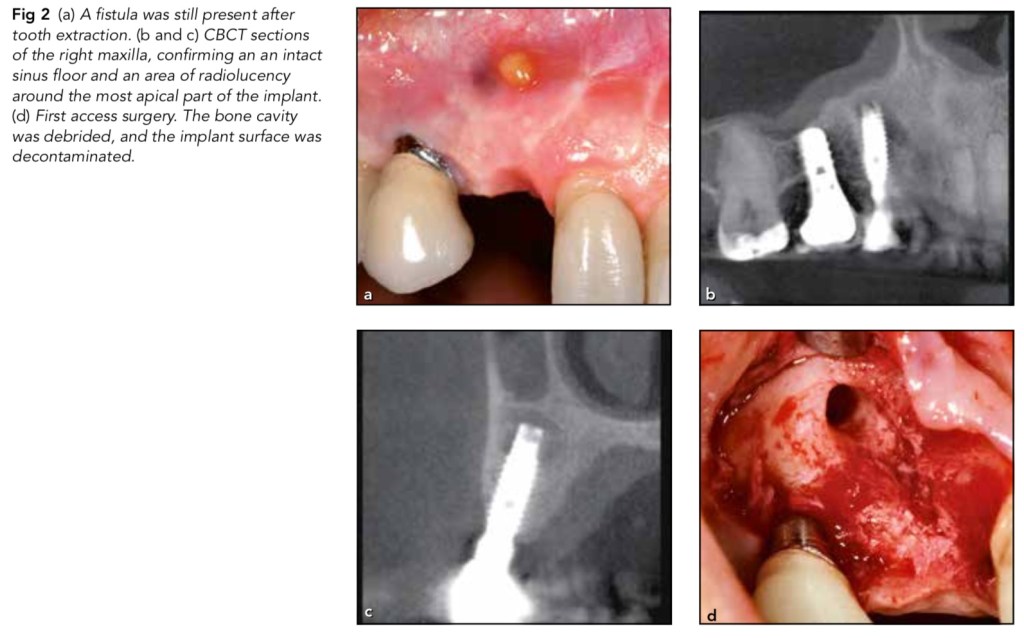

因植體周圍炎切除植體牙根之案例報告—Franceschi(2021) 2021 年 05 月 31 日2021 年 05 月 29 日 yehhsinchi 植牙 ijprd-2021-vol.41-p.443-448下載 在根尖周圍炎已經無法經傳統根管治療癒合,有根尖囊腫問題,會去做surgical endo tx去切牙根。那你有想過若是植體遇到類似的情形,可以只切植體的牙根嗎? 結果這個case report真的去切了…真的是把植體當真的牙齒了。 分享此文: 分享到 X(在新視窗中開啟) X 分享到 Facebook(在新視窗中開啟) Facebook 喜歡 正在載入...